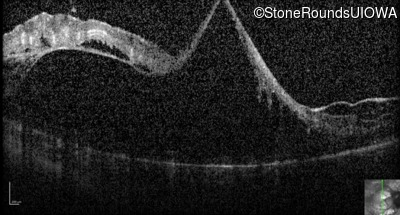

Optical Coherence Tomography - Right - 20/125 -2 sc

Exemplar / OCT Stack